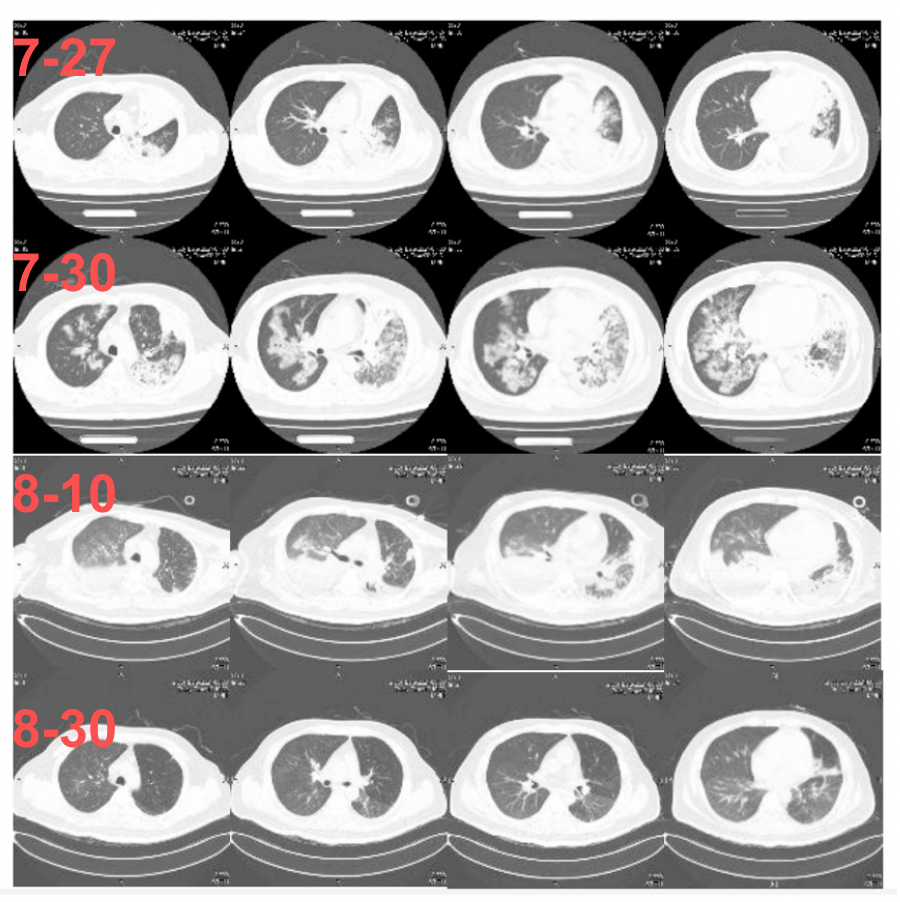

丽水市人民医院精准肺部感染治疗案例分享

图片尺寸1600x1200